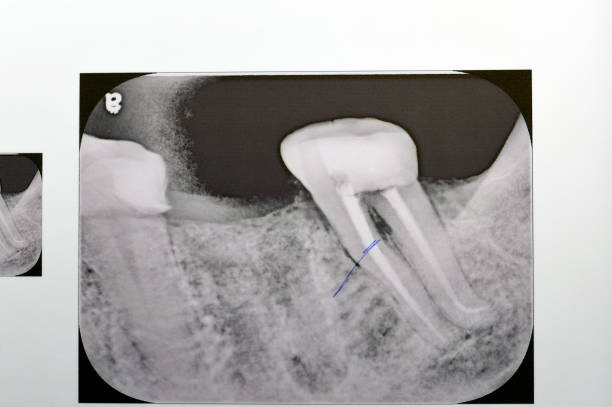

عکسهای رادیوگرافی (X-ray)، ابزار حیاتی بعدی هستن. با یه عکس دو بعدی ساده، دندانپزشک میتونه وضعیت استخوان اطراف ریشه و وجود هرگونه تغییر مشکوک مثل تحلیل استخوان رو ببینه که نشونه آبسه هست. اما گاهی وقتا، آبسهها ممکنه تو مراحل اولیه تو X-ray عادی مشخص نباشن، یا به خاطر تداخل ساختارهای دیگه پنهون بمونن.

اینجاست که پای تصویربرداری سهبعدی یا CBCT (Cone Beam Computed Tomography) به میون میاد. این تکنولوژی پیشرفته، یه دید خیلی جامعتر و دقیقتر از ساختارهای دندانی و استخوانی میده. دندانپزشک میتونه با CBCT، موقعیت دقیق آبسه، میزان گسترش عفونت و حتی کانالهای فرعی پنهان رو که ممکن بود تو X-ray عادی دیده نشن، تشخیص بده. این دقت فوقالعاده، برنامهریزی درمانی رو خیلی مطمئنتر میکنه.